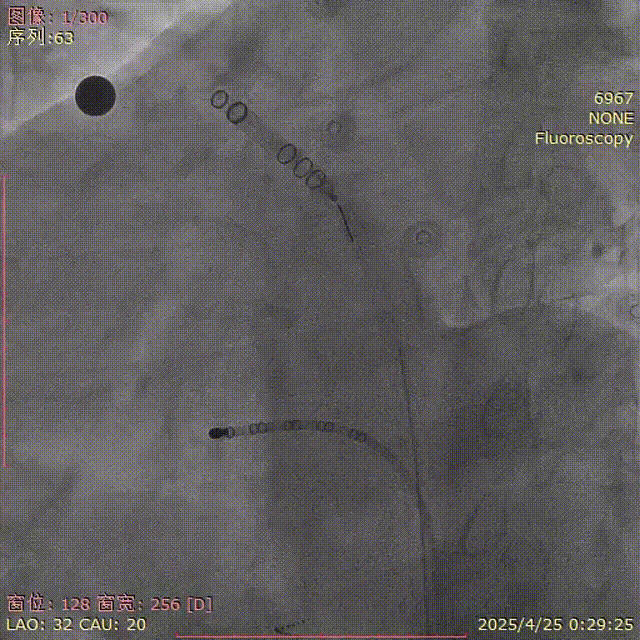

二次展开

重新调整鞘管进入上分叶,Flx Ball抵住上叶口缓慢退鞘展开封堵器。

牵拉后再造影

肝位及纯足位下缘轻微露肩(少于封堵器尺寸1/3),肩位下无明显露肩,评估符合PASS原则

LAO 30° CAU 20°

LAO 30° CRA 20°

CAU 30°